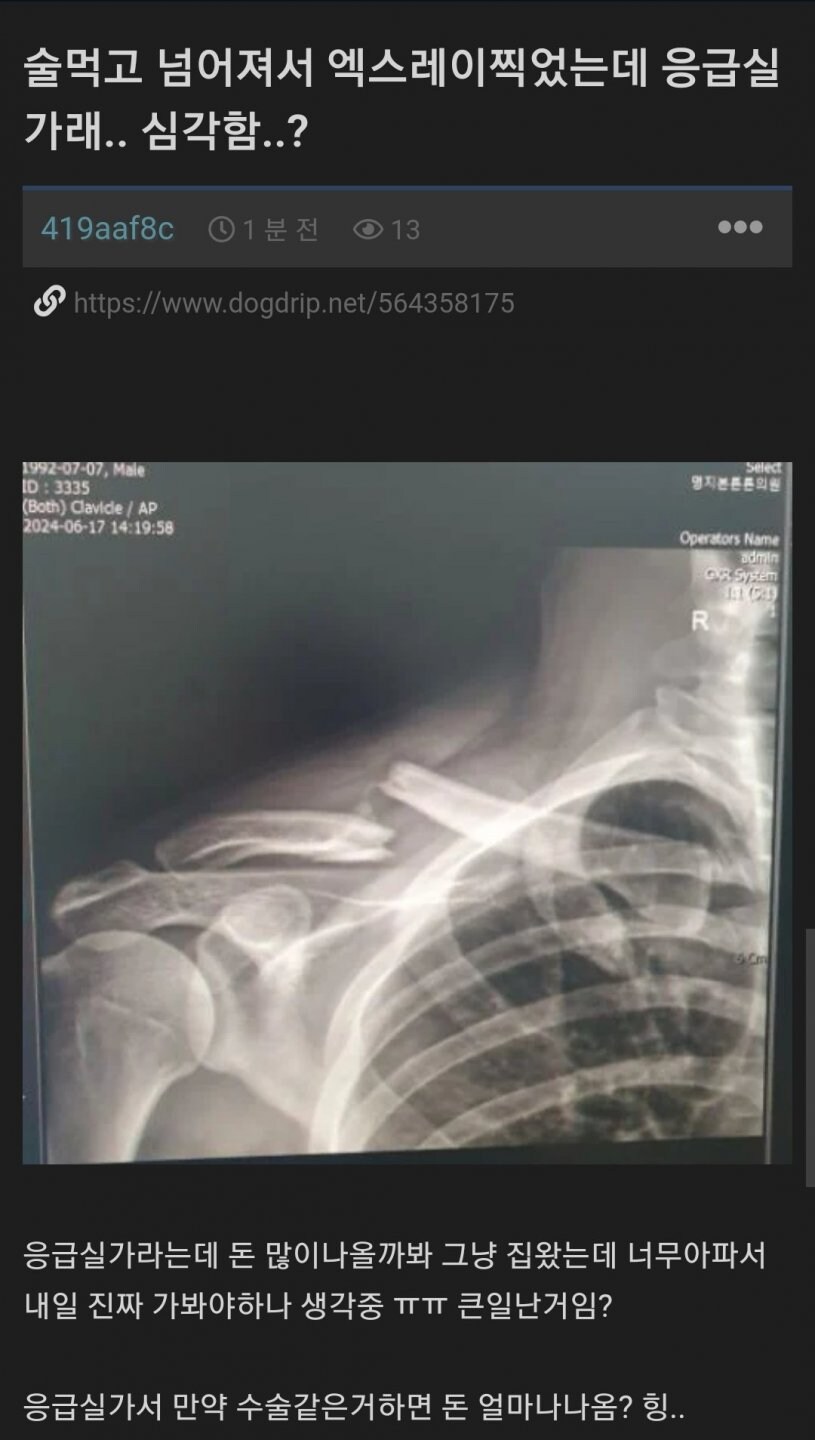

쇄골 부러졌네

금간 게 아니라 아예 뽀각나버렸다고?

쇄골 진짜 안붙는 부위인데

저상태면 오른팔 자체를 들수가 없어. 뼈가 약간만 틀어졌다면 그 상태로 고정해서 굳히면 되지만 저정도면 수술해야지